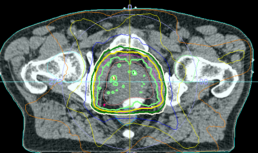

Beratung über Strahlung des Prostatakrebs

Beratung über Strahlung des Prostatakrebs : Prostatakrebs ist häufigste Tumorerkrang bei Männern. Neben der Operation, ist Strahlentherapie heutzutage eine Standardtherapie Option. Die organerhaltene Strahlentherapie ermöglicht ähnliche therapeutische Ergebnisse mit akzeptablen Nebenwirkungen. Es gibt strahlentherapeutisch für die Prostata zwei Therapie Möglichkeiten: von außen (Teleterapie) und von ihnen (Brachytherapie).

Die moderne Bestrahlungstechniken von außen (z. B. IMRT intensitämodulierte Radiotherapie mit Exact Trac Lagerunskontrolle) ermöglichen, nach Markierung der Prostata (3 Stäbchen- Goldmarker) und Abstandhalter (Spacer-Hidrogel) Implantation zwischen der Prostata und Enddarm in Allgemein oder volle Narkose, Risikoorgane (Harnblase, Darm.. ) mit reduzierten Dosen zu belasten; somit sind auch weniger potentiellen Strahlenreaktionen erwartet. Nach Beratung in gemütlicher Atmosphäre in der Ordination ist die Implantation der Goldmarker/Spacer (als Vorbereitung für präzisere und zeitgünstige Radiotherpie) in der Klinik Donaustadt an Institut für Strahlentherapie-Radioonkologie geplant